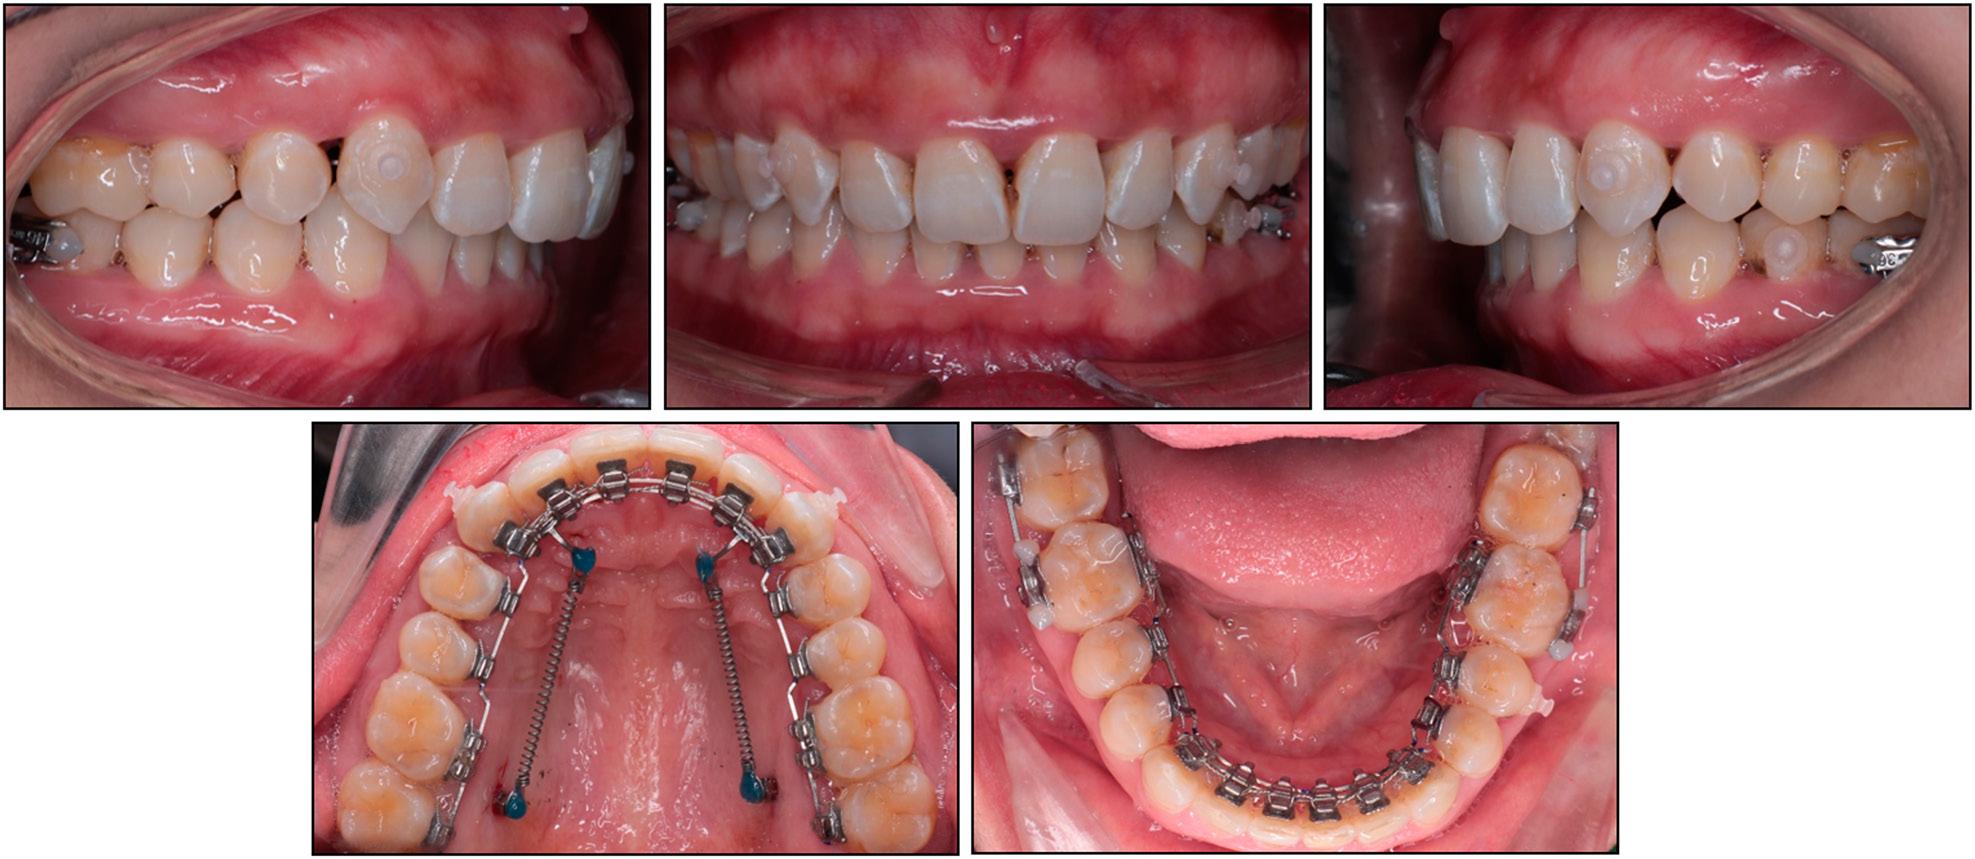

Figure 2.